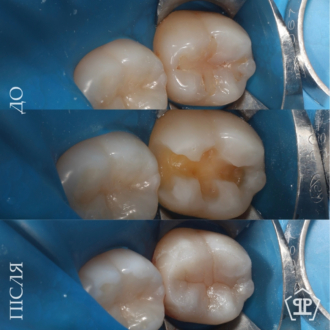

Пациент обратился с жалобами: чувство холодного воздуха и неприятные ощущения языком в области старых пломб. Было произведено полноценное удаление инфицированных тканей с последующим реставрированием зубов согласно анатомических особенностей.